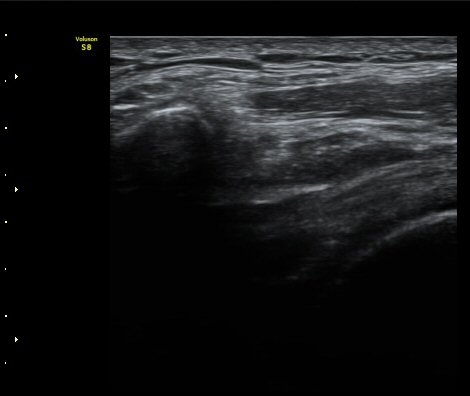

°ßºÀ¿À±¸µ¹±âÀδë Á¾´Ü¸é°Ë»ç¿¡¼­ ÀδëÀÇ ¿ÜÃø¿¡ ±¹¼ÒÀûÀÎ ÀÎ?ºñÈİ¡ °üÂûµÈ´Ù(»çÁø 3).

±Ø»ó°Ç Á¾´Ü¸é°Ë»ç½Ã ±Ø»ó°ÇÀÇ Ç¥Ãþ¿¡¼­ °üÂûµÇ´Â °ßºÀ¿À±¸µ¹±â Ⱦ´Ü¸é°Ë»ç»ó¿¡¼­

ÀδëÀÇ ºñÈİ¡ °üÂûµÈ´Ù(»çÁø 4). ±Ø»ê°ÇÀÇ Á¾´Ü¸é°Ë»ç¿Í Ⱦ´Ü¸é°Ë»ç¿¡¼­ ±Ø»ê°Ç ½ÉÃþ¿¡